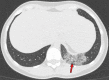

Chest CT has a potential role in the diagnosis, detection of complications, and prognostication of coronavirus disease 2019 (COVID-19). Implementation of appropriate precautionary safety measures, chest CT protocol optimization, and a standardized reporting system based on the pulmonary findings in this disease will enhance the clinical utility of chest CT. However, chest CT examinations may lead to both false-negative and false-positive results. Furthermore, the added value of chest CT in diagnostic decision making is dependent on several dynamic variables, most notably available resources (real-time reverse transcription-polymerase chain reaction [RT-PCR] tests, personal protective equipment, CT scanners, hospital and radiology personnel availability, and isolation room capacity) and the prevalence of both COVID-19 and other diseases with overlapping manifestations at chest CT. Chest CT is valuable to detect both alternative diagnoses and complications of COVID-19 (acute respiratory distress syndrome, pulmonary embolism, and heart failure), while its role for prognostication requires further investigation. The authors describe imaging and managing care of patients with COVID-19, with topics including (a) chest CT protocol, (b) chest CT findings of COVID-19 and its complications, (c) the diagnostic accuracy of chest CT and its role in diagnostic decision making and prognostication, and (d) reporting and communicating chest CT findings. The authors also review other specific topics, including the pathophysiology and clinical manifestations of COVID-19, the World Health Organization case definition, the value of performing RT-PCR tests, and the radiology department and personnel impact related to performing chest CT in COVID-19. ©RSNA, 2020.